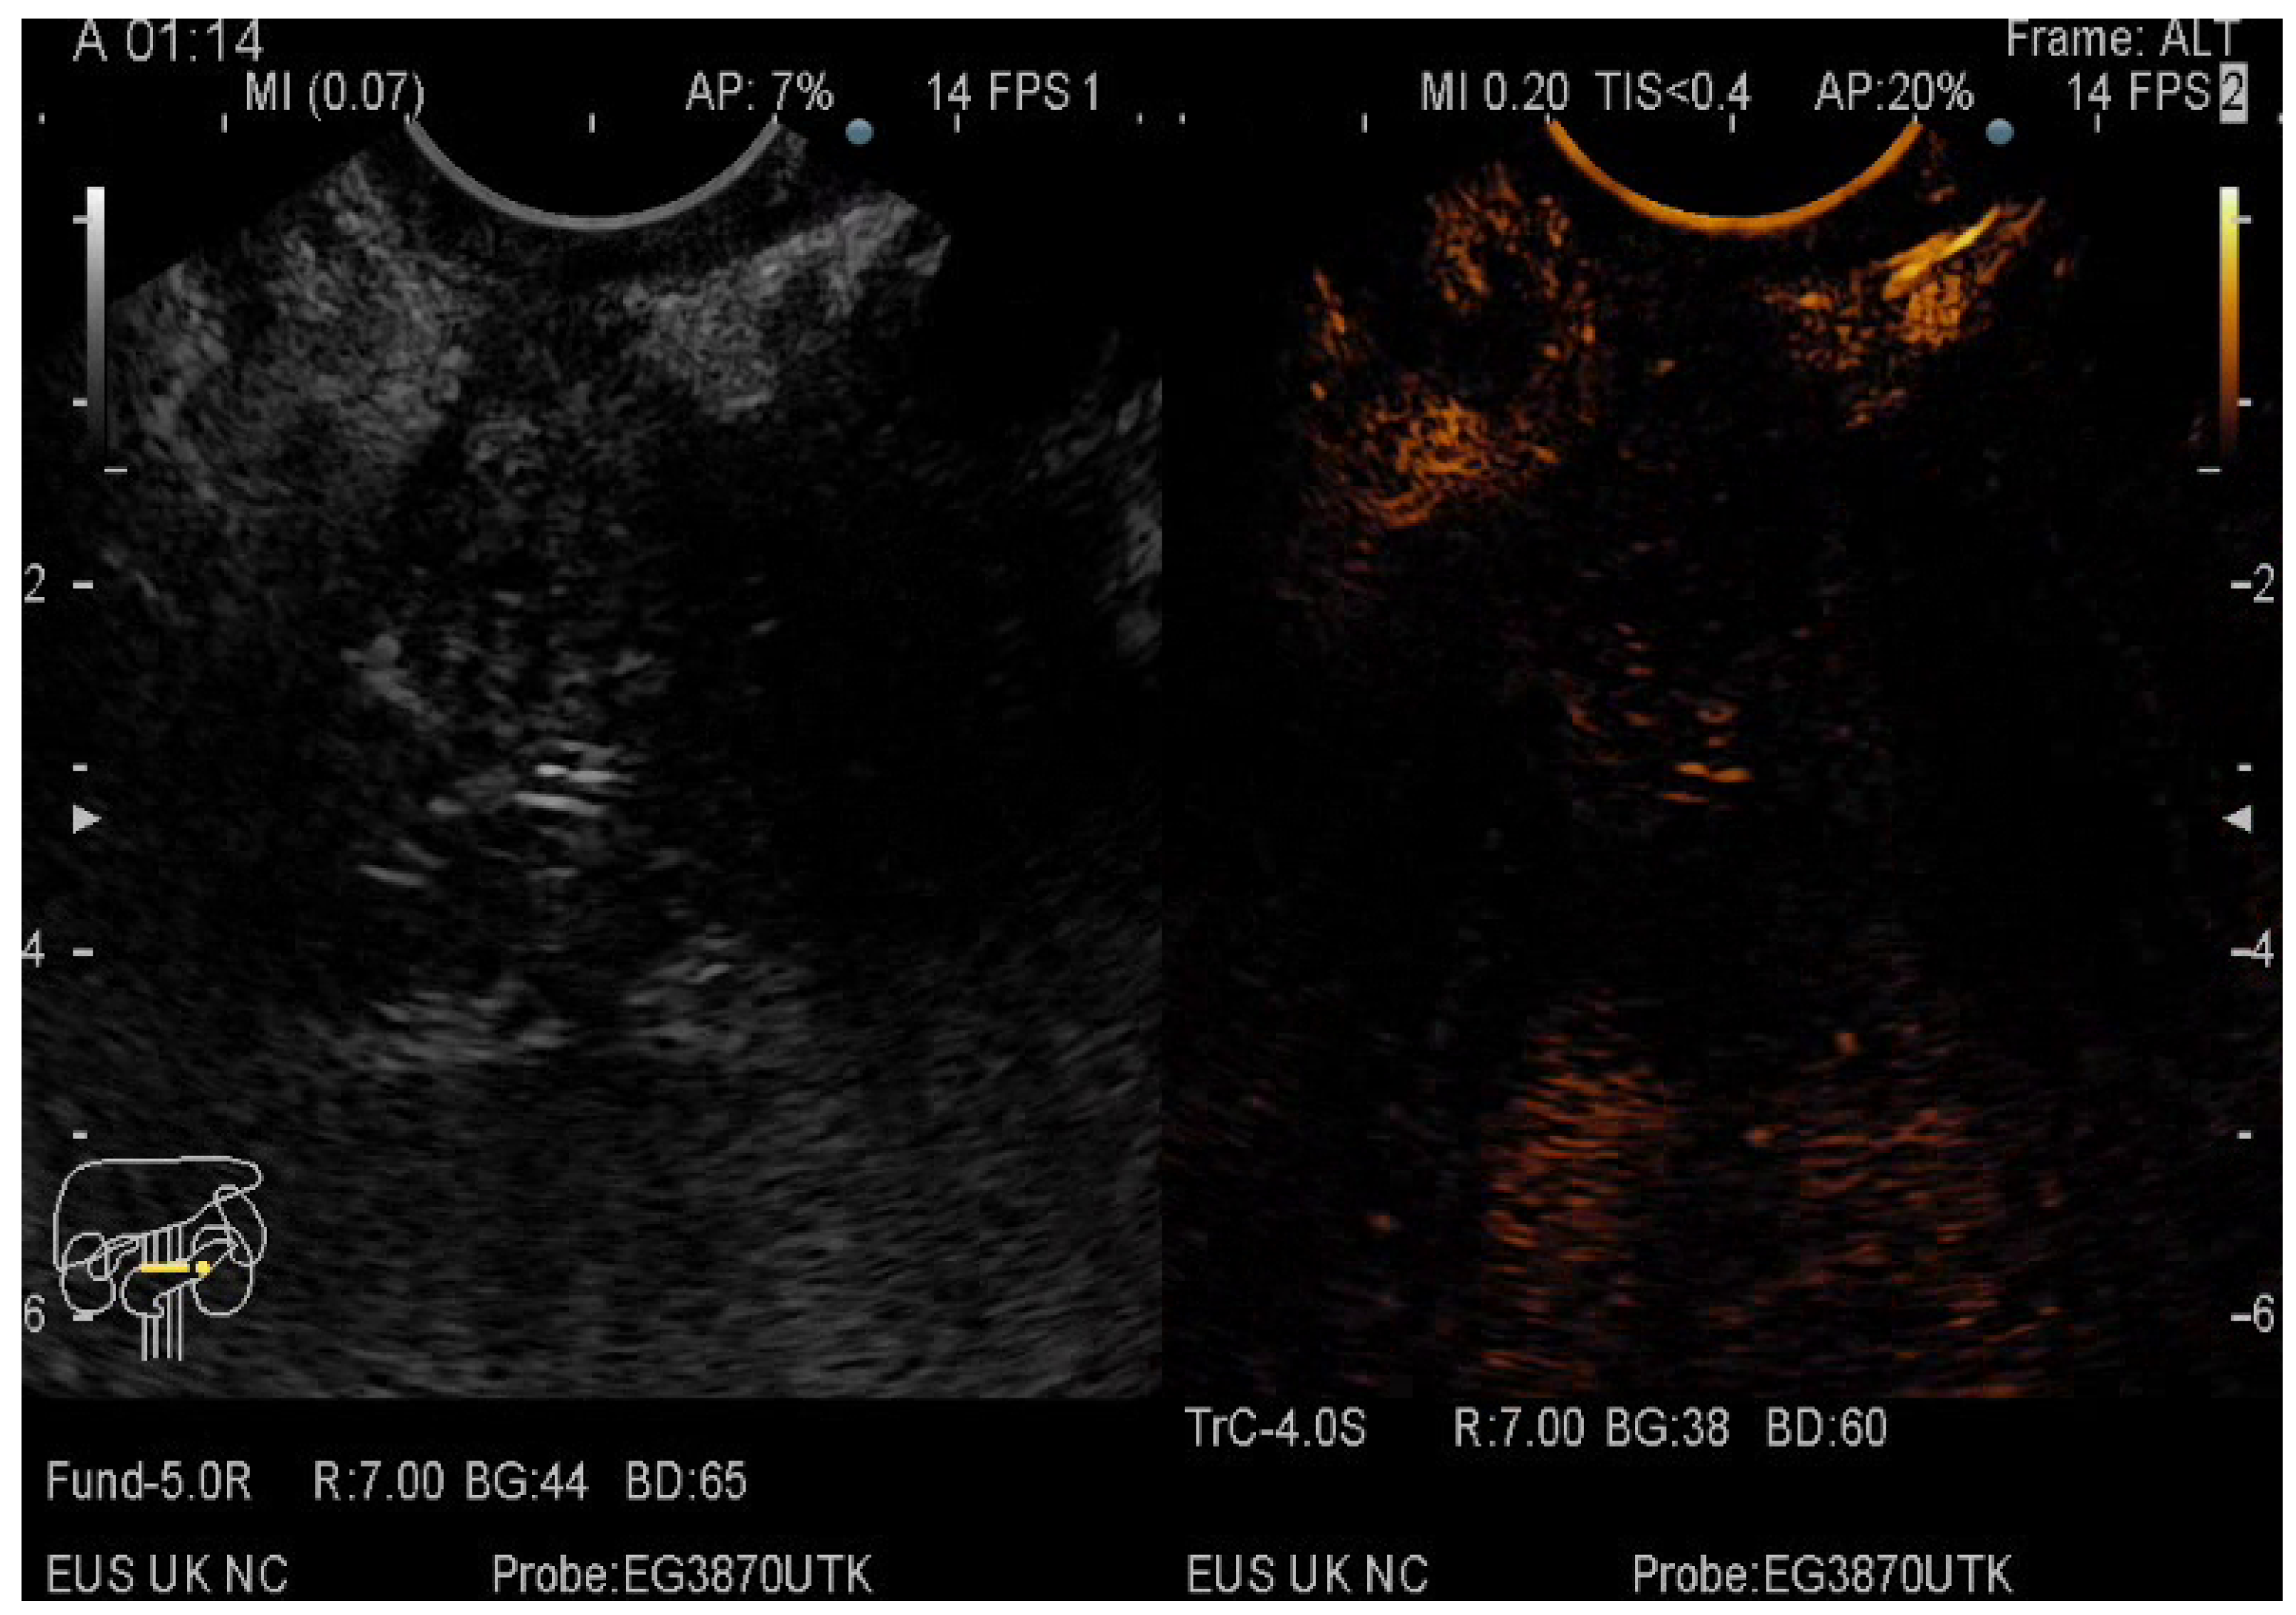

2.5. CE-EUS Procedure

3.3. EUS-FNA/FNB + CE-EUS of Pancreatic Cystic Lesions Subgroup